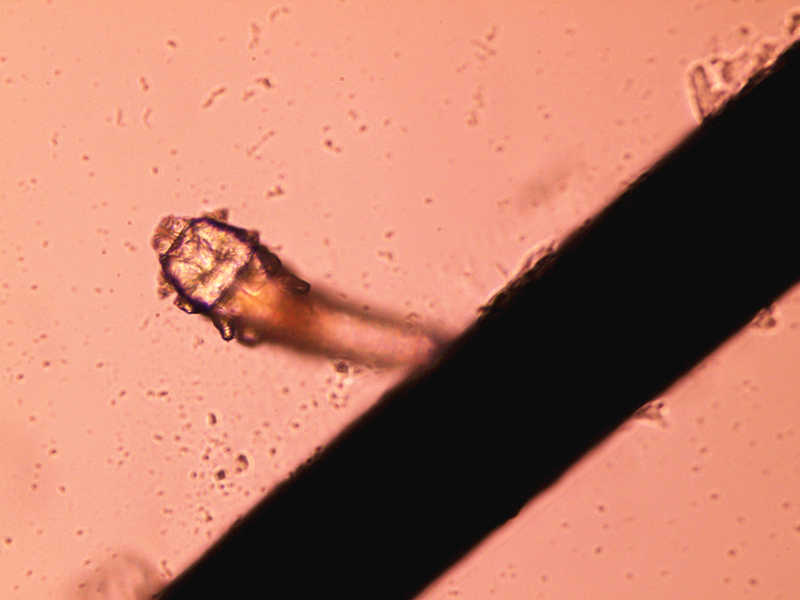

“你的眼睑上有寄生虫!”被别人这样说你一定会受到很大的冲击吧。不过,这可不是危言耸听,据资料统计,我国人体蠕形螨的感染率较高,据报道最高达到98%以上。因为人体对螨虫的感染无免疫性,不同年龄,不同民族,不同性别均可感染。蠕形螨广泛存在于自然界,迄今只有两个种类发现寄居于人体体表,即毛囊蠕形螨和皮脂蠕形螨。而寄居在人类眼睑上的睫毛蠕形螨以食睫毛毛囊上皮细胞和代谢产物为生,其代谢废物和死亡躯体常导致睫毛根部圆柱状或袖套样鳞屑,导致睑缘炎。

蠕形螨寄居眼部临床表现轻重不一,从无任何不适到睑缘充血,痒,刺痛感,异物感等睑缘炎典型体征,蠕形螨导致的睑缘炎常反复发作,难彻底治愈,在睑缘常发现鳞屑存在。因此,当你发现顽固不愈,反复发作的鳞屑性睑缘炎,必需警惕蠕形螨感染的可能。